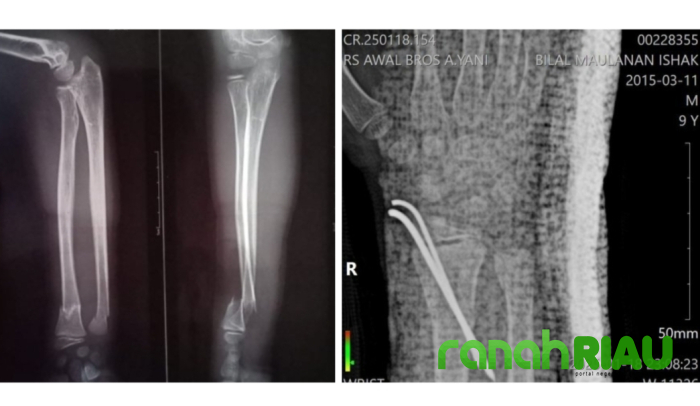

Dari hasil pemeriksaan, ternyata korban mengalami patah tulang tangan setelah terjatuh dari mobil dump truk ketika bermain dengan teman-temannya.

" Iya, sudah dilakukan operasi RSUD Teluk Kuantan. Setelah dioperasi, Bilal kembali dironsen, tapi kata dokter posisi tulang nya gak bisa kembali. Emang harus dipasang Pen. Kan di RSUD cuma dipasang gips oleh dokter," papar Murniati.

Setelah operasi di RSUD Teluk Kuantan gagal, sambung Murniati, kemudian dokter RY merujuk Bilal ke rumah sakit Awal bros Ahmad Yani pada tanggal 18 Januari 2025 untuk menjalani operasi kedua.

" Alhamdulillah setelah operasi ke dua di RS Awal Bros Ahmad Yani, posisi tulang sudah kembali, karena dokter sudah memasang pen. Tanggal 20 kemarin itu sesuai hasil rekam medis nomor 00228355 departemen pucuk rebung/361, yang diterima oleh dr. Petrus Aprianto, SpOT., AIFO-K, FICS, Bilal sudah diperbolehkan pulang. Dengan catatan, tanggal 31 Januari nanti kami ke Pekanbaru lagi untuk melakukan kontrol," pungkasnya.